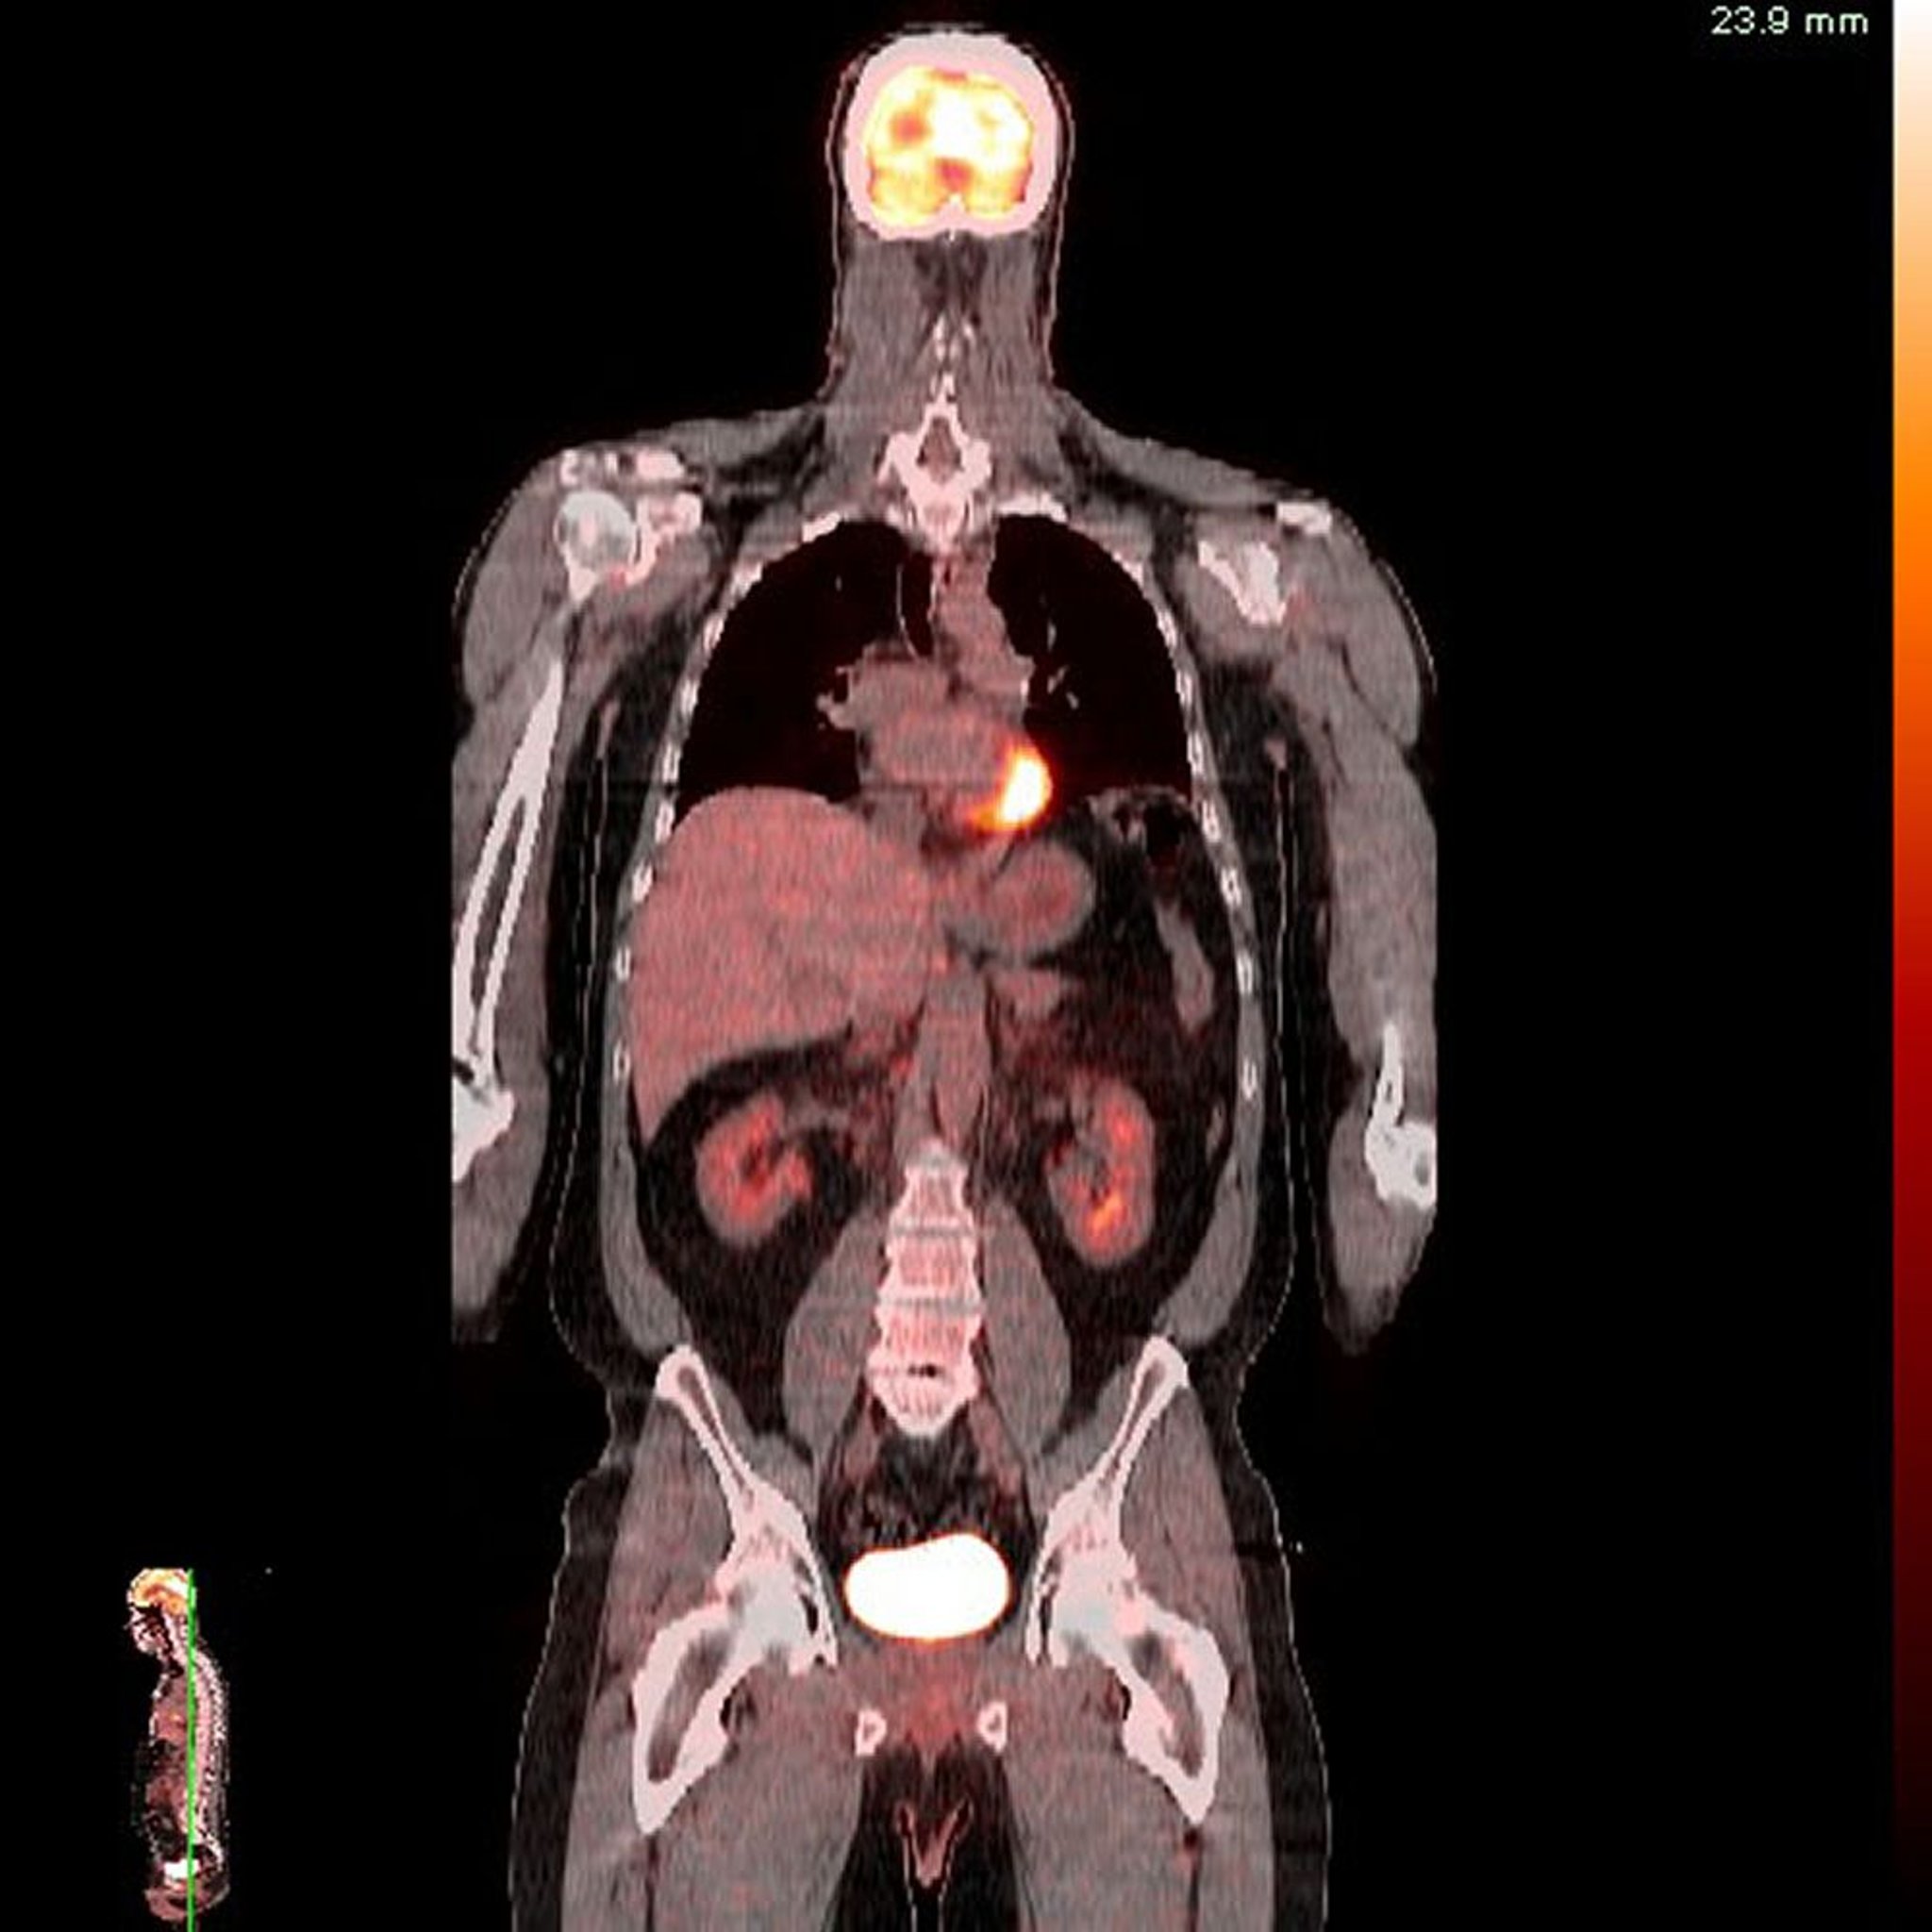

पॉज़िट्रॉन एमिशन टोमोग्राफ़ी (PET) एक तरह की चिकित्सा इमेजिंग है, जिसे रेडियोन्यूक्लाइड स्कैनिंग कहा जाता है। रेडियोएक्टिव पदार्थ दिए जाने के बाद उसके रेडिएशन को स्कैन करके PET ऐसी इमेज बनाता है, जिनसे किसी ऊतक की कार्यक्षमता की जानकारी मिल सकती है और असामान्य ऊतक को पहचानने में मदद मिल सकती है।

PET में, ऐसा पदार्थ जिसे शरीर उपयोग करता है (मेटाबोलिज़्म करता है), जैसे कि ग्लूकोज़ या ऑक्सीजन, को रेडियोन्यूक्लाइड के साथ लेबल किया जाता है। इस पदार्थ और रेडियोन्यूक्लाइड के कॉम्बिनेशन को रेडियोएक्टिव ट्रेसर कहा जाता है। ट्रेसर शरीर के खास ऊतकों में जमा हो जाता है। आमतौर पर, ऊतक जितना ज़्यादा सक्रिय होता है (उदाहरण के लिए, वह ग्लूकोज़ या ऑक्सीजन का जितना ज़्यादा इस्तेमाल करता है), उतना ही ज़्यादा ट्रेसर वहां पर जमा होता है और वह उतनी ही ज़्यादा रेडिएशन देता है।

ये इमेज रंग की विभिन्न तीव्रता (इंटेंसिटी) में गतिविधि के विभिन्न स्तरों को दिखाती हैं। इस तरह, PET ऊतक के काम करने के बारे में जानकारी दे सकता है और असामान्य ऊतकों की पहचान कर सकता है, जो सामान्य ऊतकों की तुलना में अधिक या कम सक्रिय हो सकते हैं। हालांकि, PET, ऊतकों और अंगों की शारीरिक और संरचनात्मक जानकारी को कंप्यूटेड टोमोग्राफ़ी (CT) या मैग्नेटिक रीसोनेंस इमेजिंग (MRI) जितनी अच्छी तरह नहीं दिखाता है।

PET करने से यह पता चल सकता है कि कैंसर कहां है, यह कहां फैल गया है और इलाज करने पर यह कैसी प्रतिक्रिया दे रहा है।

लगभग 80% PET स्कैन इसलिए किए जाते हैं, ताकि डॉक्टरों को कैंसर का मूल्यांकन करने में मदद मिल सके। इन कैंसरों में फेफड़े का कैंसर, कोलोरेक्टल कैंसर, इसोफ़ेजियल कैंसर, सिर और गर्दन का कैंसर, लिम्फ़ोमा और मेलेनोमा शामिल हैं।

PET कंप्यूटेड टोमोग्राफ़ी (PET-CT)

PET का उपयोग आमतौर पर कंप्यूटेड टोमोग्राफ़ी (CT) के साथ किया जाता है। PET-CT से, शरीर की रचना (CT के माध्यम से) और कार्य (PET के माध्यम से) को दिखाते हुए ज़्यादा जानकारी देने वाली 2-डायमेंशनल इमेज मिलती है। दोनों इमेज (CT और PET इमेज) को अलग-अलग देखा जा सकता है, या एक को दूसरे के ऊपर रखकर देखा जा सकता है। इस प्रकार, यह तकनीक शरीर की रचना और कार्य दोनों के बारे में उपयोगी जानकारी प्रदान करती है और डॉक्टरों को उन असामान्यताओं की पहचान करने में मदद कर सकती है जो शरीर रचना और/या कार्य को प्रभावित करती हैं।

यह तकनीक शरीर के उन हिस्सों के कैंसर का पता लगाने के लिए बहुत उपयोगी है जिनमें गर्दन और श्रोणि जैसे कई अलग-अलग ऊतक एक साथ आबद्ध होते हैं। इससे कैंसर का सही पता लगाने में मदद मिलती है और शुरुआत में ही दोबारा होने जैसी घटनाओं के बारे पता चल सकता है।